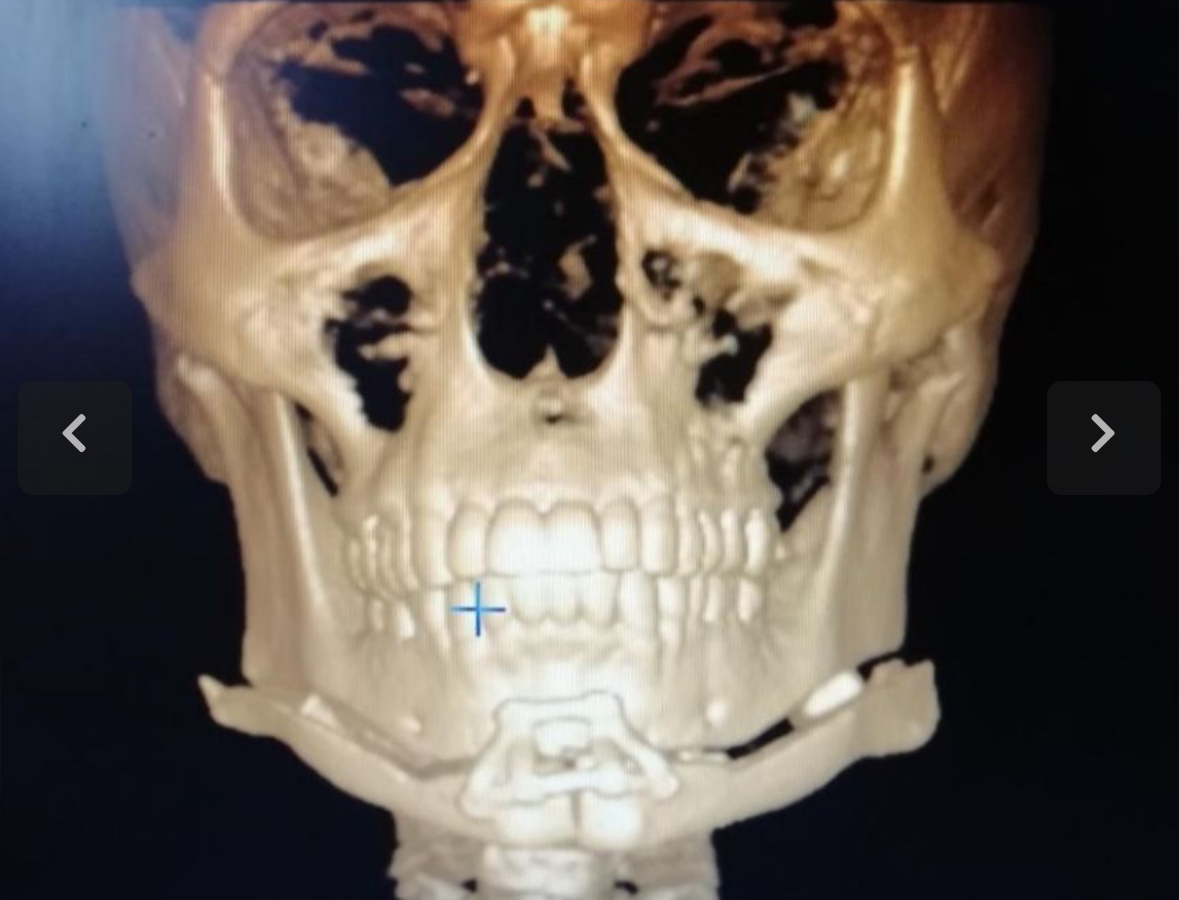

I have a narrow upper jaw so I’m going to see a doctor on the 10th of April to see if I can get a sarpe.

Would a sarpe and then lefort 1 (make my maxilla more prominent) paired with a bimax and genio(fix my lower third) make this morph slightly possible? Ofc I know that it’s impossible to even replicate this morph irl. Just want your thoughts on the direction of procedures that could make it look similar .

I have a narrow upper jaw so I’m going to see a doctor on the 10th of April to see if I can get a sarpe.

Would a sarpe and then lefort 1 (make my maxilla more prominent) paired with a bimax and genio(fix my lower third) make this morph slightly possible? Ofc I know that it’s impossible to even replicate this morph irl. Just want your thoughts on the direction of procedures that could make it look similar .